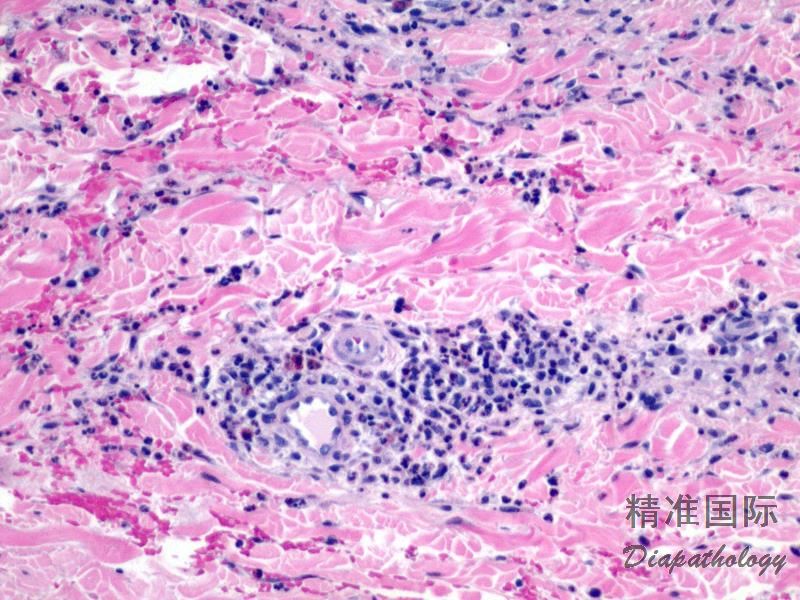

真皮过敏反应

Dermal Hypersensitivity Reaction